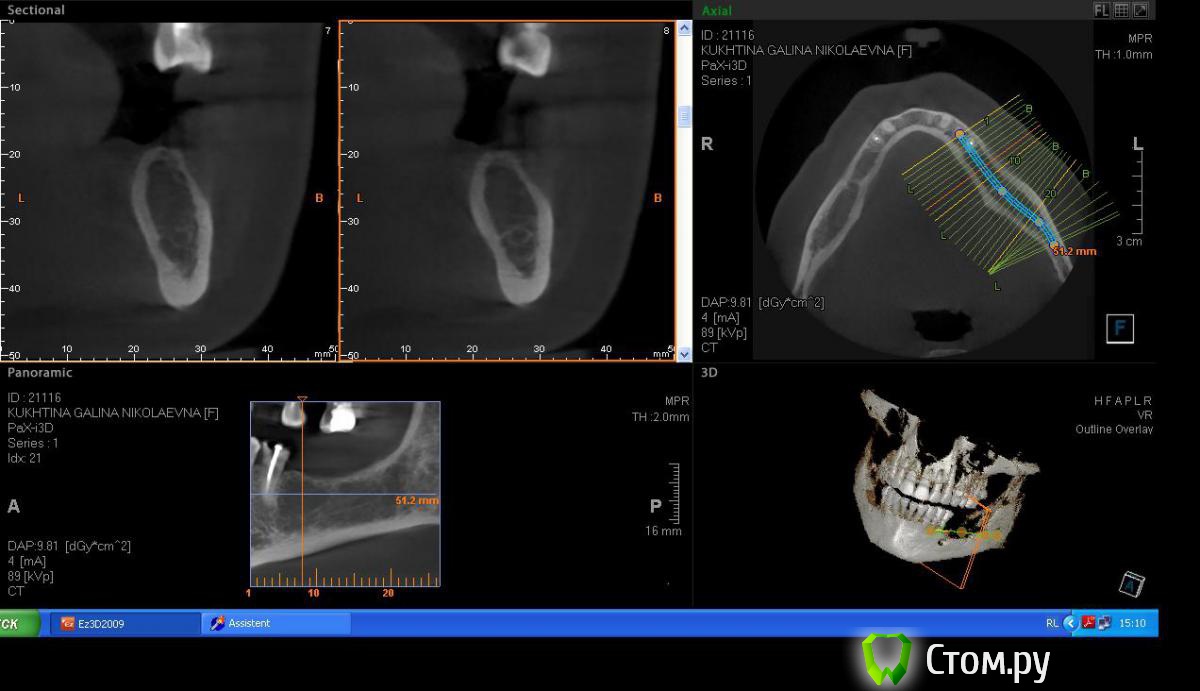

Пишем пациенту (45 лет, женщина) план ортопедического лечения, возможно с имплантами, возможно нет, пока думаем.

привлек внимание беззубый участок 36,37 зубов, уж очень большая лакуна получается, как вы думаете, онкология возможна или просто структура кости такая.

Если структура такова (склоняюсь к этому варианту, основываясь на отсутствии клиники, по контрастности на снимке, не отягощенн. анамнез), то как считаете, первичной стабильности имплантата добьемся за счет кортикалки? Или лучше в подобню яму не лезть и придумать бюгель, с другой стороны нет только 5,6,7.

Во рту клиники никакой нет.На орто ничего не видно. Жалоб нет.

прикрепил снимки в инверсии, лучше видно))